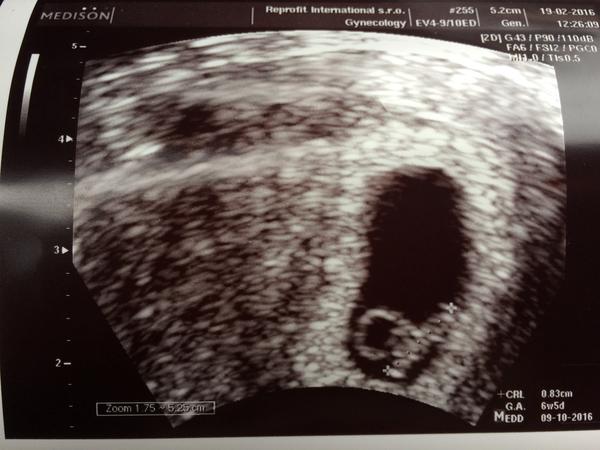

Tak zítra na mě prosím myslete, jdu na potvrzení srdíčka. Už mi je sice líp, ale pořád soplím a kašlu, tak snad to prcek zvládnul.

@drndapetka Moc gratuluji k srdíčku a přeji pohodové těhotenství 🙂

@drndapetka Gatuluju,krásná fotečka!Taky se chystám v uterý na Ket v nativu.Máme doma už jednu Reprofitačku-1,5r.Předtím jsem měla Ket stimulovaný,tak nevím zda to vyjde.Vždycky jsem otěhotněla,ale 2x potratila.A poslední pokus uspěšný.Naše poslední embryo.Naše poslední šance.Tak uvidíme.Držím palce a snad tě budu nýsledovat 🙂